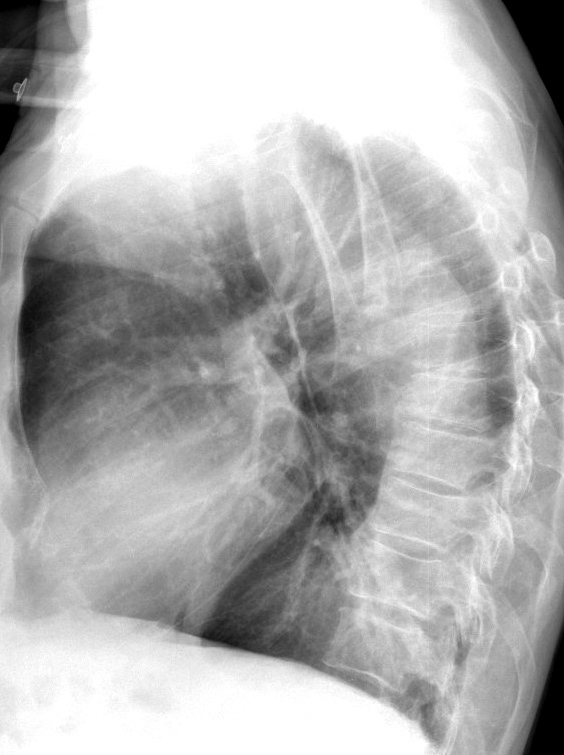

Gallery Aorta Dissection Ao Diss 1b

Ao Diss 1b